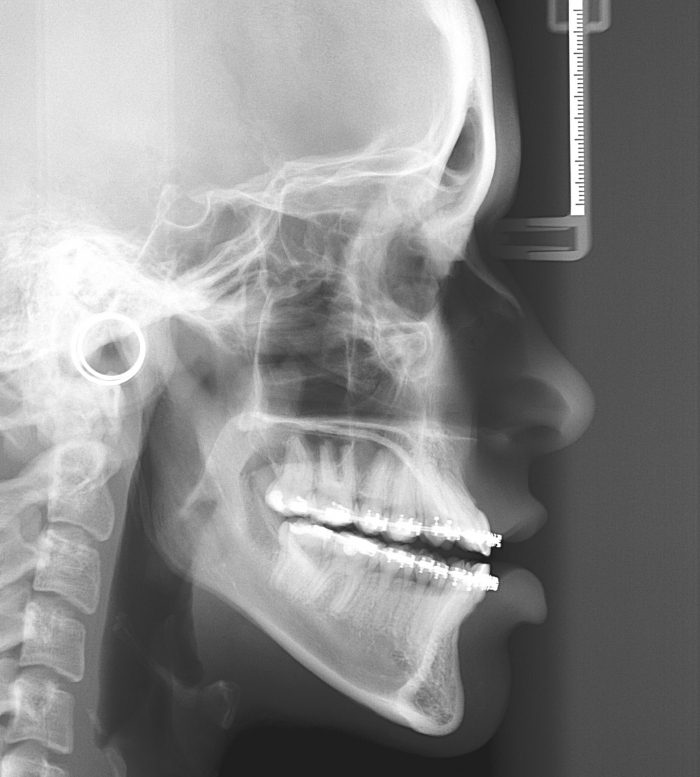

Telerradiografia inicial

Telerradiografia após a cirurgia